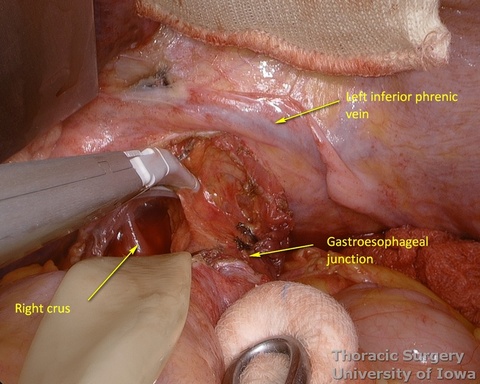

- The peritoneum is incised around the hiatus.

- The phrenoesophageal ligament is divided and the right crus dissected.

- The abdominal esophagus, periesophageal fat, and nodes are dissected and encircled with a Penrose drain for retraction.

- The mediastinum is entered with the combination of sharp and blunt dissection. Note that postradiation adhesions become denser 4-6 weeks after neoadjuvant treatment.

- Once the mediastinum entered, the manual palpation through the hiatus is performed to assess mobility of the esophagus. Tumor is “rocked” from side to side to make sure it is not adherent to the aorta, prevertebral fascia, or mediastinal structures, thus assuring the feasibility of transhiatal approach or the need to perform transthoracic dissection. This should also be planned based on preoperative imaging.